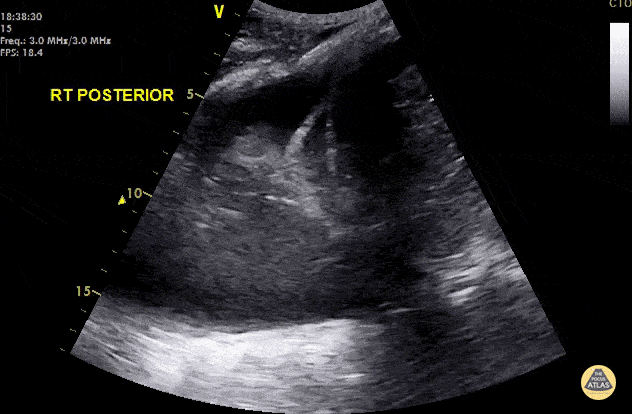

Pulmonary - Jellyfish Sign

Hypotensive septic elderly male. Right lung base shows a positive spine sign, jellyfish sign and shred sign indicating right basal pneumonia and a parapneumonic pleural effusion. Dr. Cian McDermott - Dublin, Ireland A spine sign occurs when fluid or consolidation in the lung allows for transmission and visualization of the spine superior to the diaphragm. A jellyfish sign represents compressed and airless (atelectatic) lung tissue floating within an effusion, also known as "lung flapping." The shred sign is a hyperechoic artifact created at the transition point between solidified (pathologic) and aerated lung.